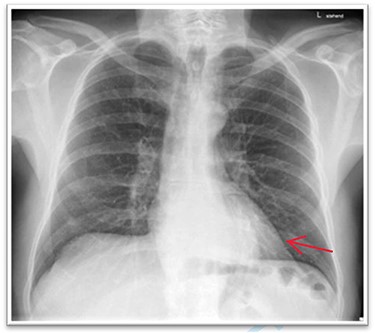

A 63-year-old male patient underwent a medical check-up due to acute bronchitis. The patient’s body mass index was 24.7 kg/m2, he was in good physical condition and no further pathological findings were revealed during clinical examination. Chest X-ray showed a retrocardiac mass (Fig. 1) and a subsequent CT scan indicated a lipomatous mass in the lower posterior mediastinum measuring 10 × 4.4 × 10.6 cm. A vascular pedicle reaching into the abdominal cavity suggested paraesophageal herniation of a large portion of the greater omentum (Fig. 2). The patient was referred to the surgical department suffering from a retrosternal feeling of pressure aggravated in supine position, with a differential diagnosis of lipomatous tumour. No symptoms of gastroesophageal reflux disease were reported, and the clinical examination showed no abnormalities. Preoperative work-up included a gastroscopy and contrast medium swallow. Endoscopy showed an axial hernia of 4 cm without further irregularities or signs of a reflux disease. Passage appeared physiological with no signs of gastroesophageal reflux and orthotopic positioning of the oesophagogastric junction.